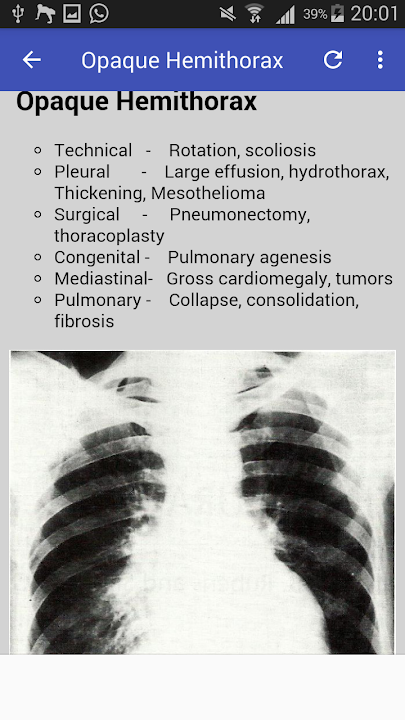

This app was designed to teach clinically the relevant aspects of chest pathology to medical students, junior doctors, radiology residents, consultant radiologists, consultant pulmonologists and all allied medical professionals providing or interpreting chest radiology.

It also teaches on how to recognizebasic radiological signs, pathology and pattern associated with common medical conditions as seen on plain PA and AP radiographs .